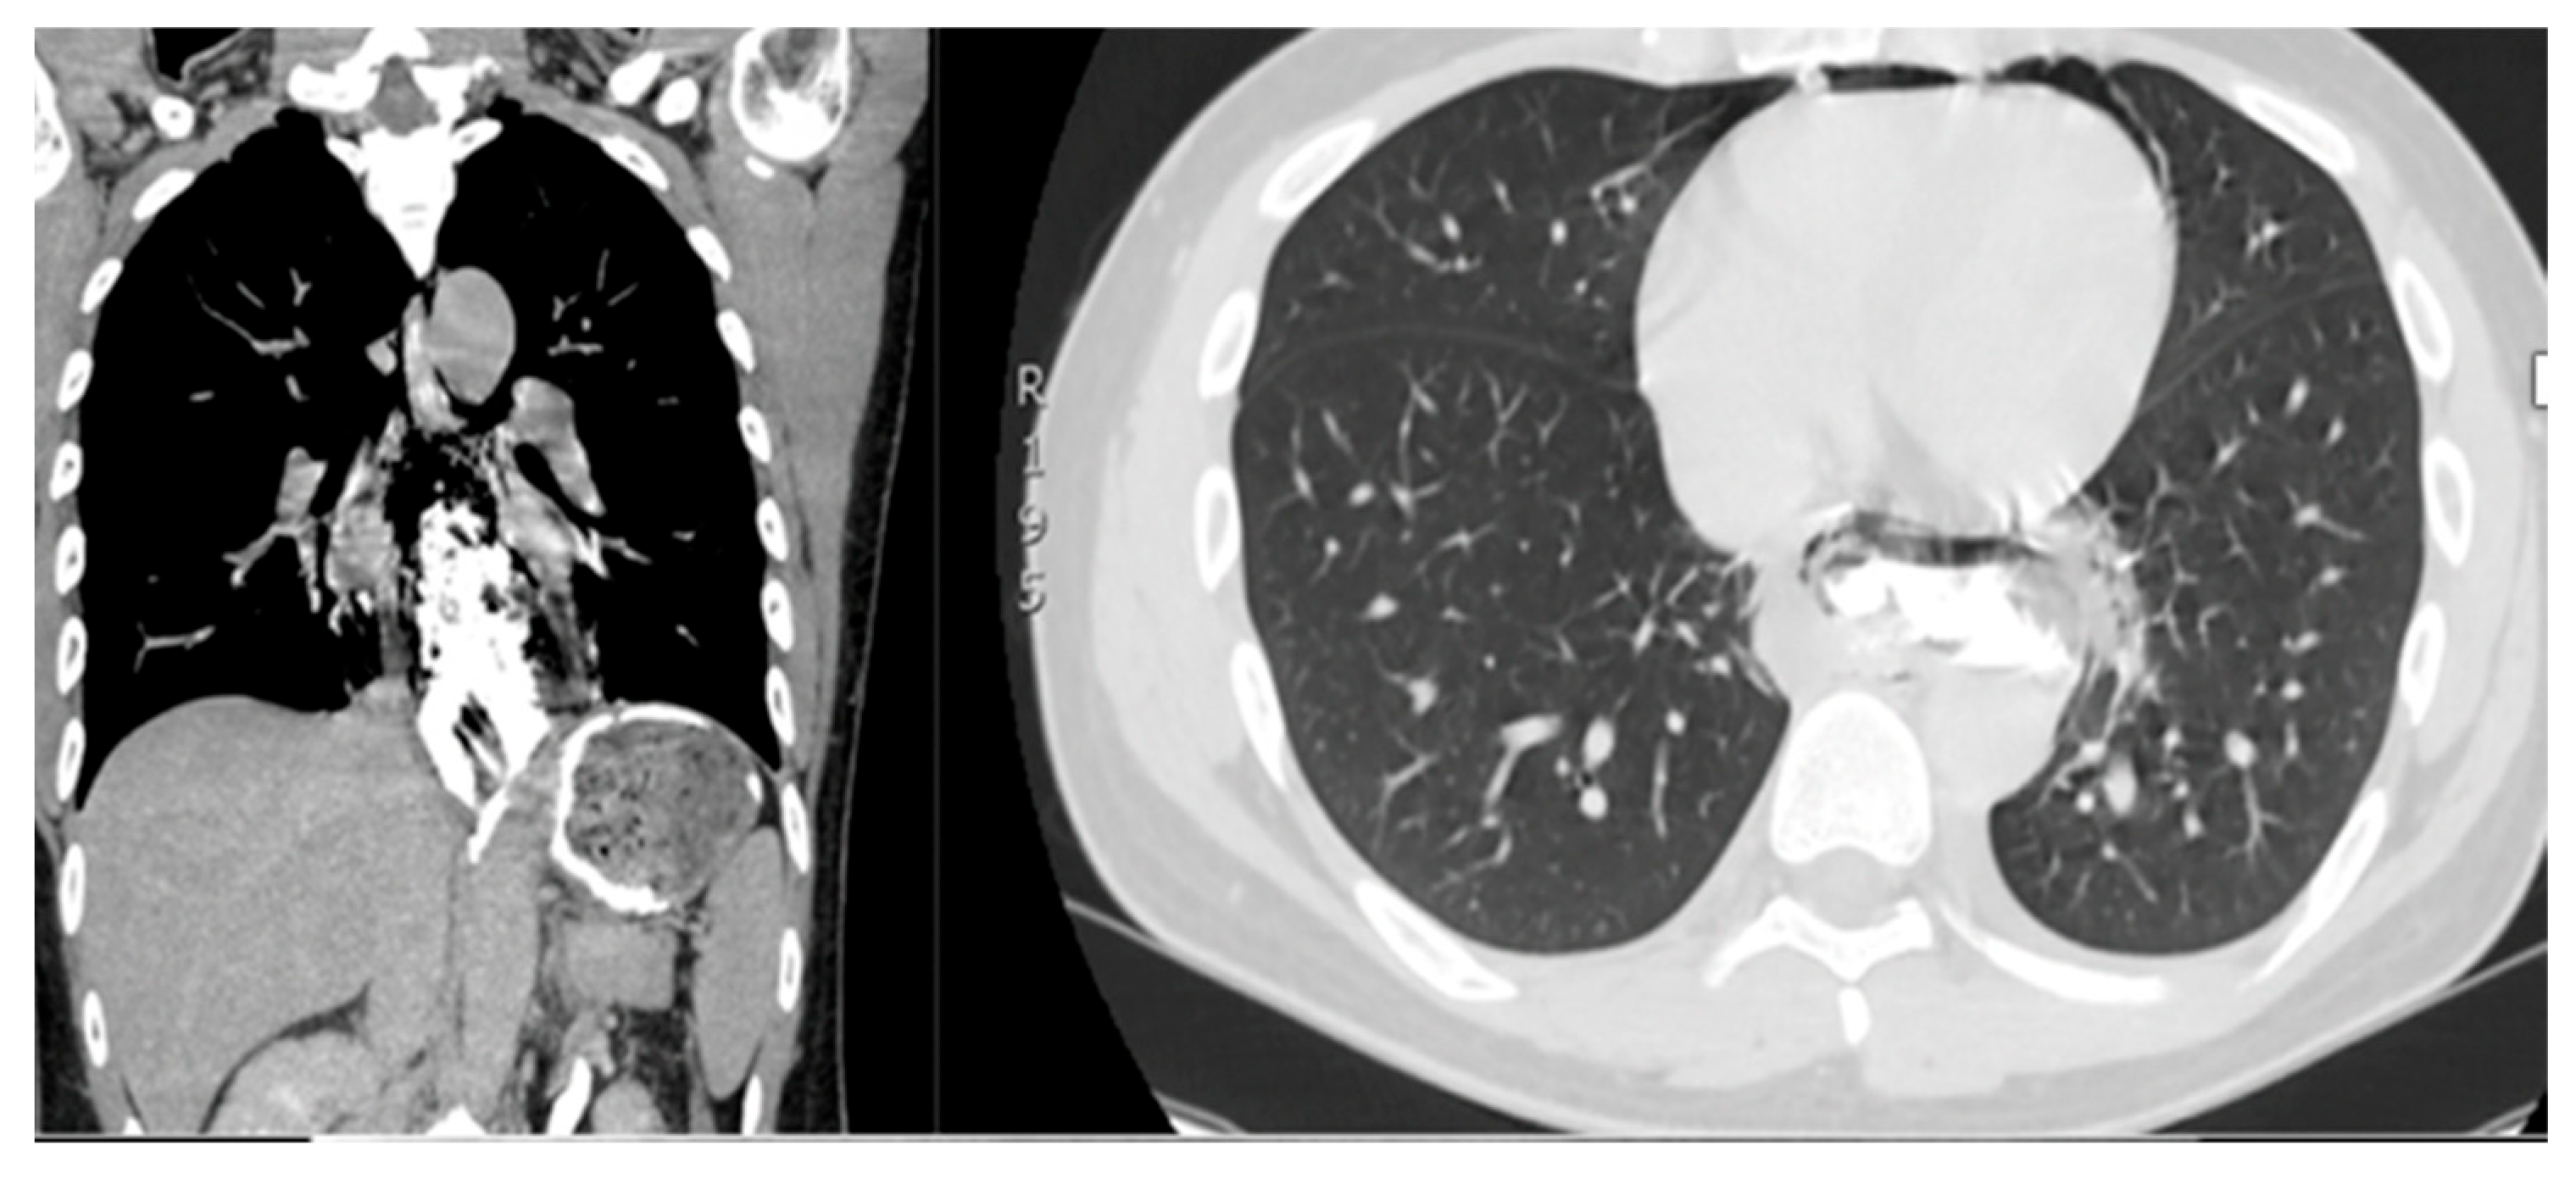

2.2. Diagnosis and Symptoms